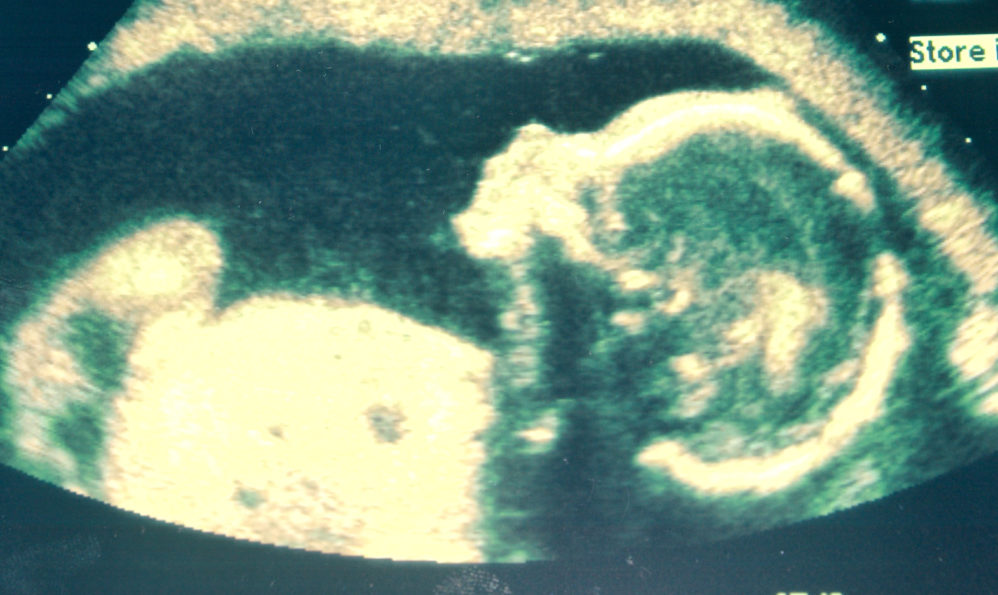

But Vermont, and other pro-abortion states, are increasingly becoming out of the mainstream. Many Americans cannot be fooled. In the years since the tragic Roe v. Wade decision in 1973, modern technology such as the ultrasound machine has provided conclusive proof that the preborn child is not a “blob of tissue,” the dismissive claim of abortion advocates, but a living, breathing, and feeling person, made in the image of God and deserving of life. It is the abortion advocates who are in denial of reality, not those who believe in the right to life.